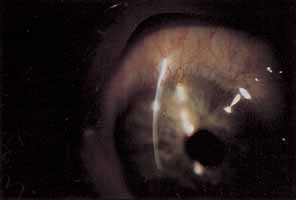

STERILE INFILTRATES

Sterile corneal infiltrates associated with contact lens wear are generally multiple, small, anterior stromal infiltrates found most often at the corneal limbus but also in clusters in the central cornea (Fig. 4).130–132 Rarely the epithelium alone may be involved and is commonly intact over stromal infiltrates. The anterior chamber may show mild to severe cellular reaction.130 Corneal infiltrates related to extended soft lens wear tend to form near the superior limbus.133 These infiltrates must be distinguished from their infectious counterparts, including chlamydia, by careful historical consideration and clinical examination.131 If there is any doubt regarding the etiology of the infiltrates, scrapings for stain and culture should be taken, followed by appropriate broad-spectrum topical antibiotic therapy.

Fig. 4 Twelve o'clock sterile marginal corneal infiltrate.